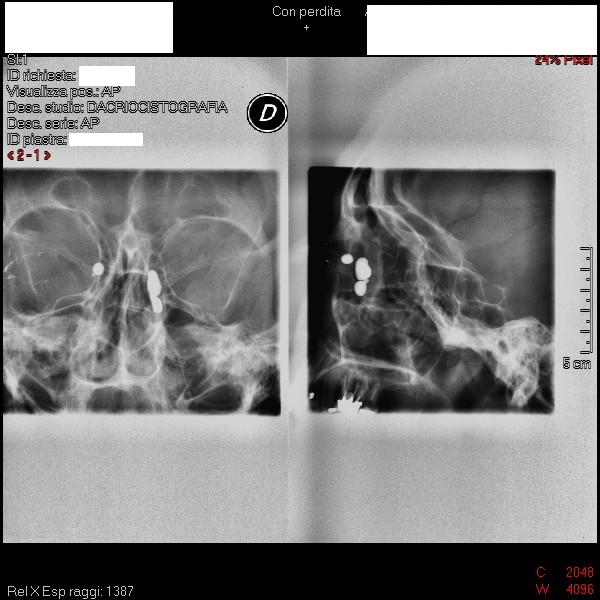

Paziente di 53 anni, riferiti episodi di dacriocistiti acute occhio destro.

Già effettuata dacriocistotac che ha evidenziato ostruzione delle vie lacrimali.

Prescritta terapia medica e programmata dacriocistorinostomia per via endoscopica nasale